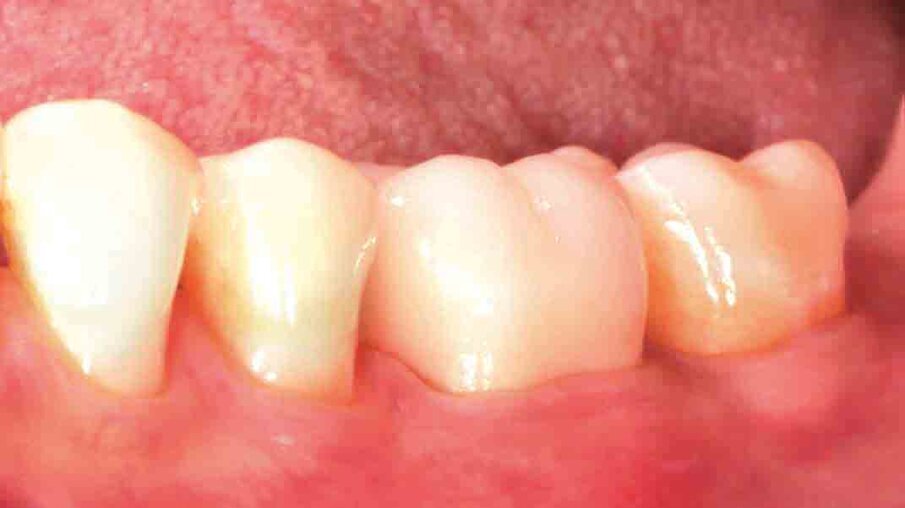

Fig. 4: Following tooth preparation, a temporary crown is produced chairside with 3M™ Protemp™ 4 Temporization Material. This material exhibits a high strength and a natural gloss without polishing.

Fig. 5: One week after the preparation procedure, healthy soft tissue conditions are obtained. They lay the foundation for a high-quality precision impression.